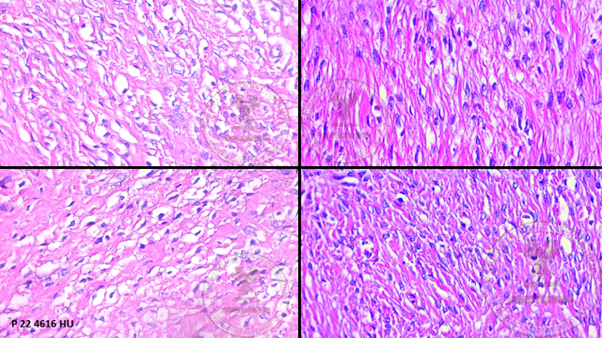

Histological images

1. Panoramic view of the ovary showing the ovarian capsule, proliferation of bundles of spindle cells surrounded by a collagenous stroma accompanied by medium-caliber vessels. (HYE, 4x).

1. Proliferation of bundles of spindle cells surrounded by a collagenous stroma (H&E 10x).

1. Spindle-shaped cells with ovoid nuclei with pointed ends and scant eosinophilic cytoplasm with the presence of lipid inclusions that mixes with the surrounding eosinophilic stroma (HYE 40x).